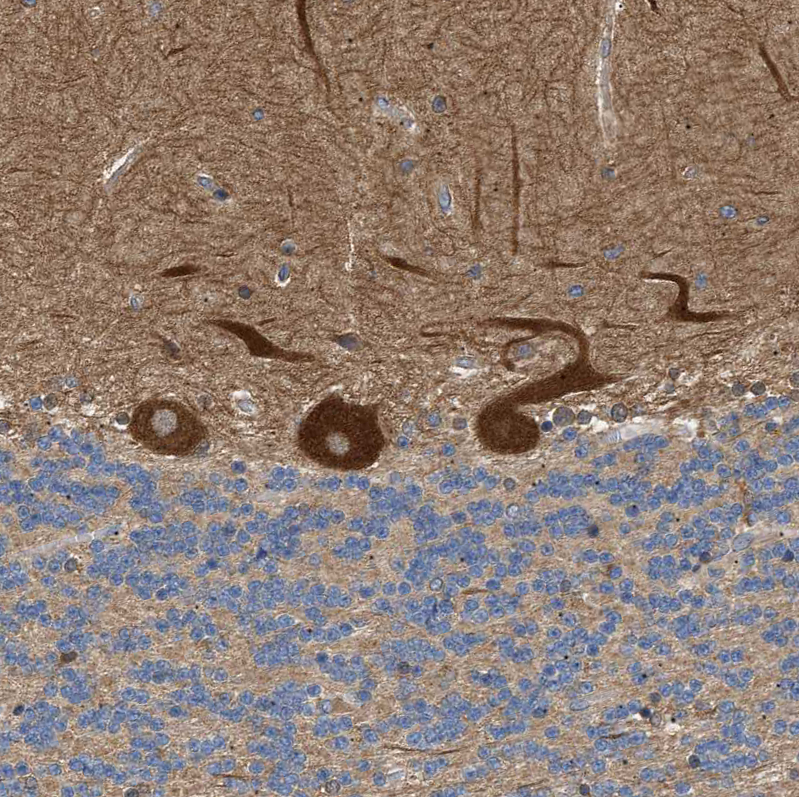

Immunohistochemical staining of human cerebellum shows strong cytoplasmic positivity in Purkinje cells.